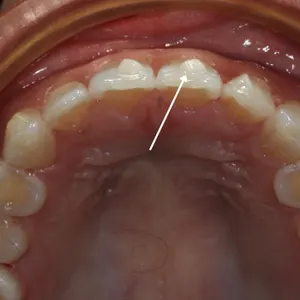

This is where there is spacing (gaps) present between the teeth. These spaces usually appear between the two upper or lower front teeth – this is known as a Diastema. A diastema usually happens due to reasons such as:

• A mismatch of the size of the jawbone and the teeth.

• A high labial frenum attachment -if you have a high labial frenum attachment then you could be suitable for a frenectomy and then orthodontics afterward to resolve this.

• Missing or undersized teeth – when some teeth are missing or smaller than others this can cause a diastema to develop. This is common when the upper lateral incisors are miss??

• Thumb sucking as a child is also a common reason for spacing in between teeth and diastema, this is due to the teeth pulling forward from the unnatural force.

A diastema isn’t seen as a ‘dental problem’ they are usually harmless and need no correction. Some people see a diastema as a characteristic that adds personality to their smile, like Madonna for example.

However, with dental spacing, we usually hear complaints of food becoming stuck in between the teeth, or in some cases, people don’t like the aesthetics of spacing or diastema. In that case, orthodontic treatment can be done to correct this.

A dental midline shift is a condition where the centerline of the upper and lower teeth is not aligned properly with the center of the face. In other words, the midline of the upper teeth is not directly above the midline of the lower teeth. This can result in an asymmetrical appearance of the teeth and the face.

A dental midline shift can be caused by a variety of factors, including tooth loss, genetics, facial trauma, or improper dental treatment. Depending on the severity of the condition, treatment options may include orthodontic treatment, dental restoration, or even jaw surgery.